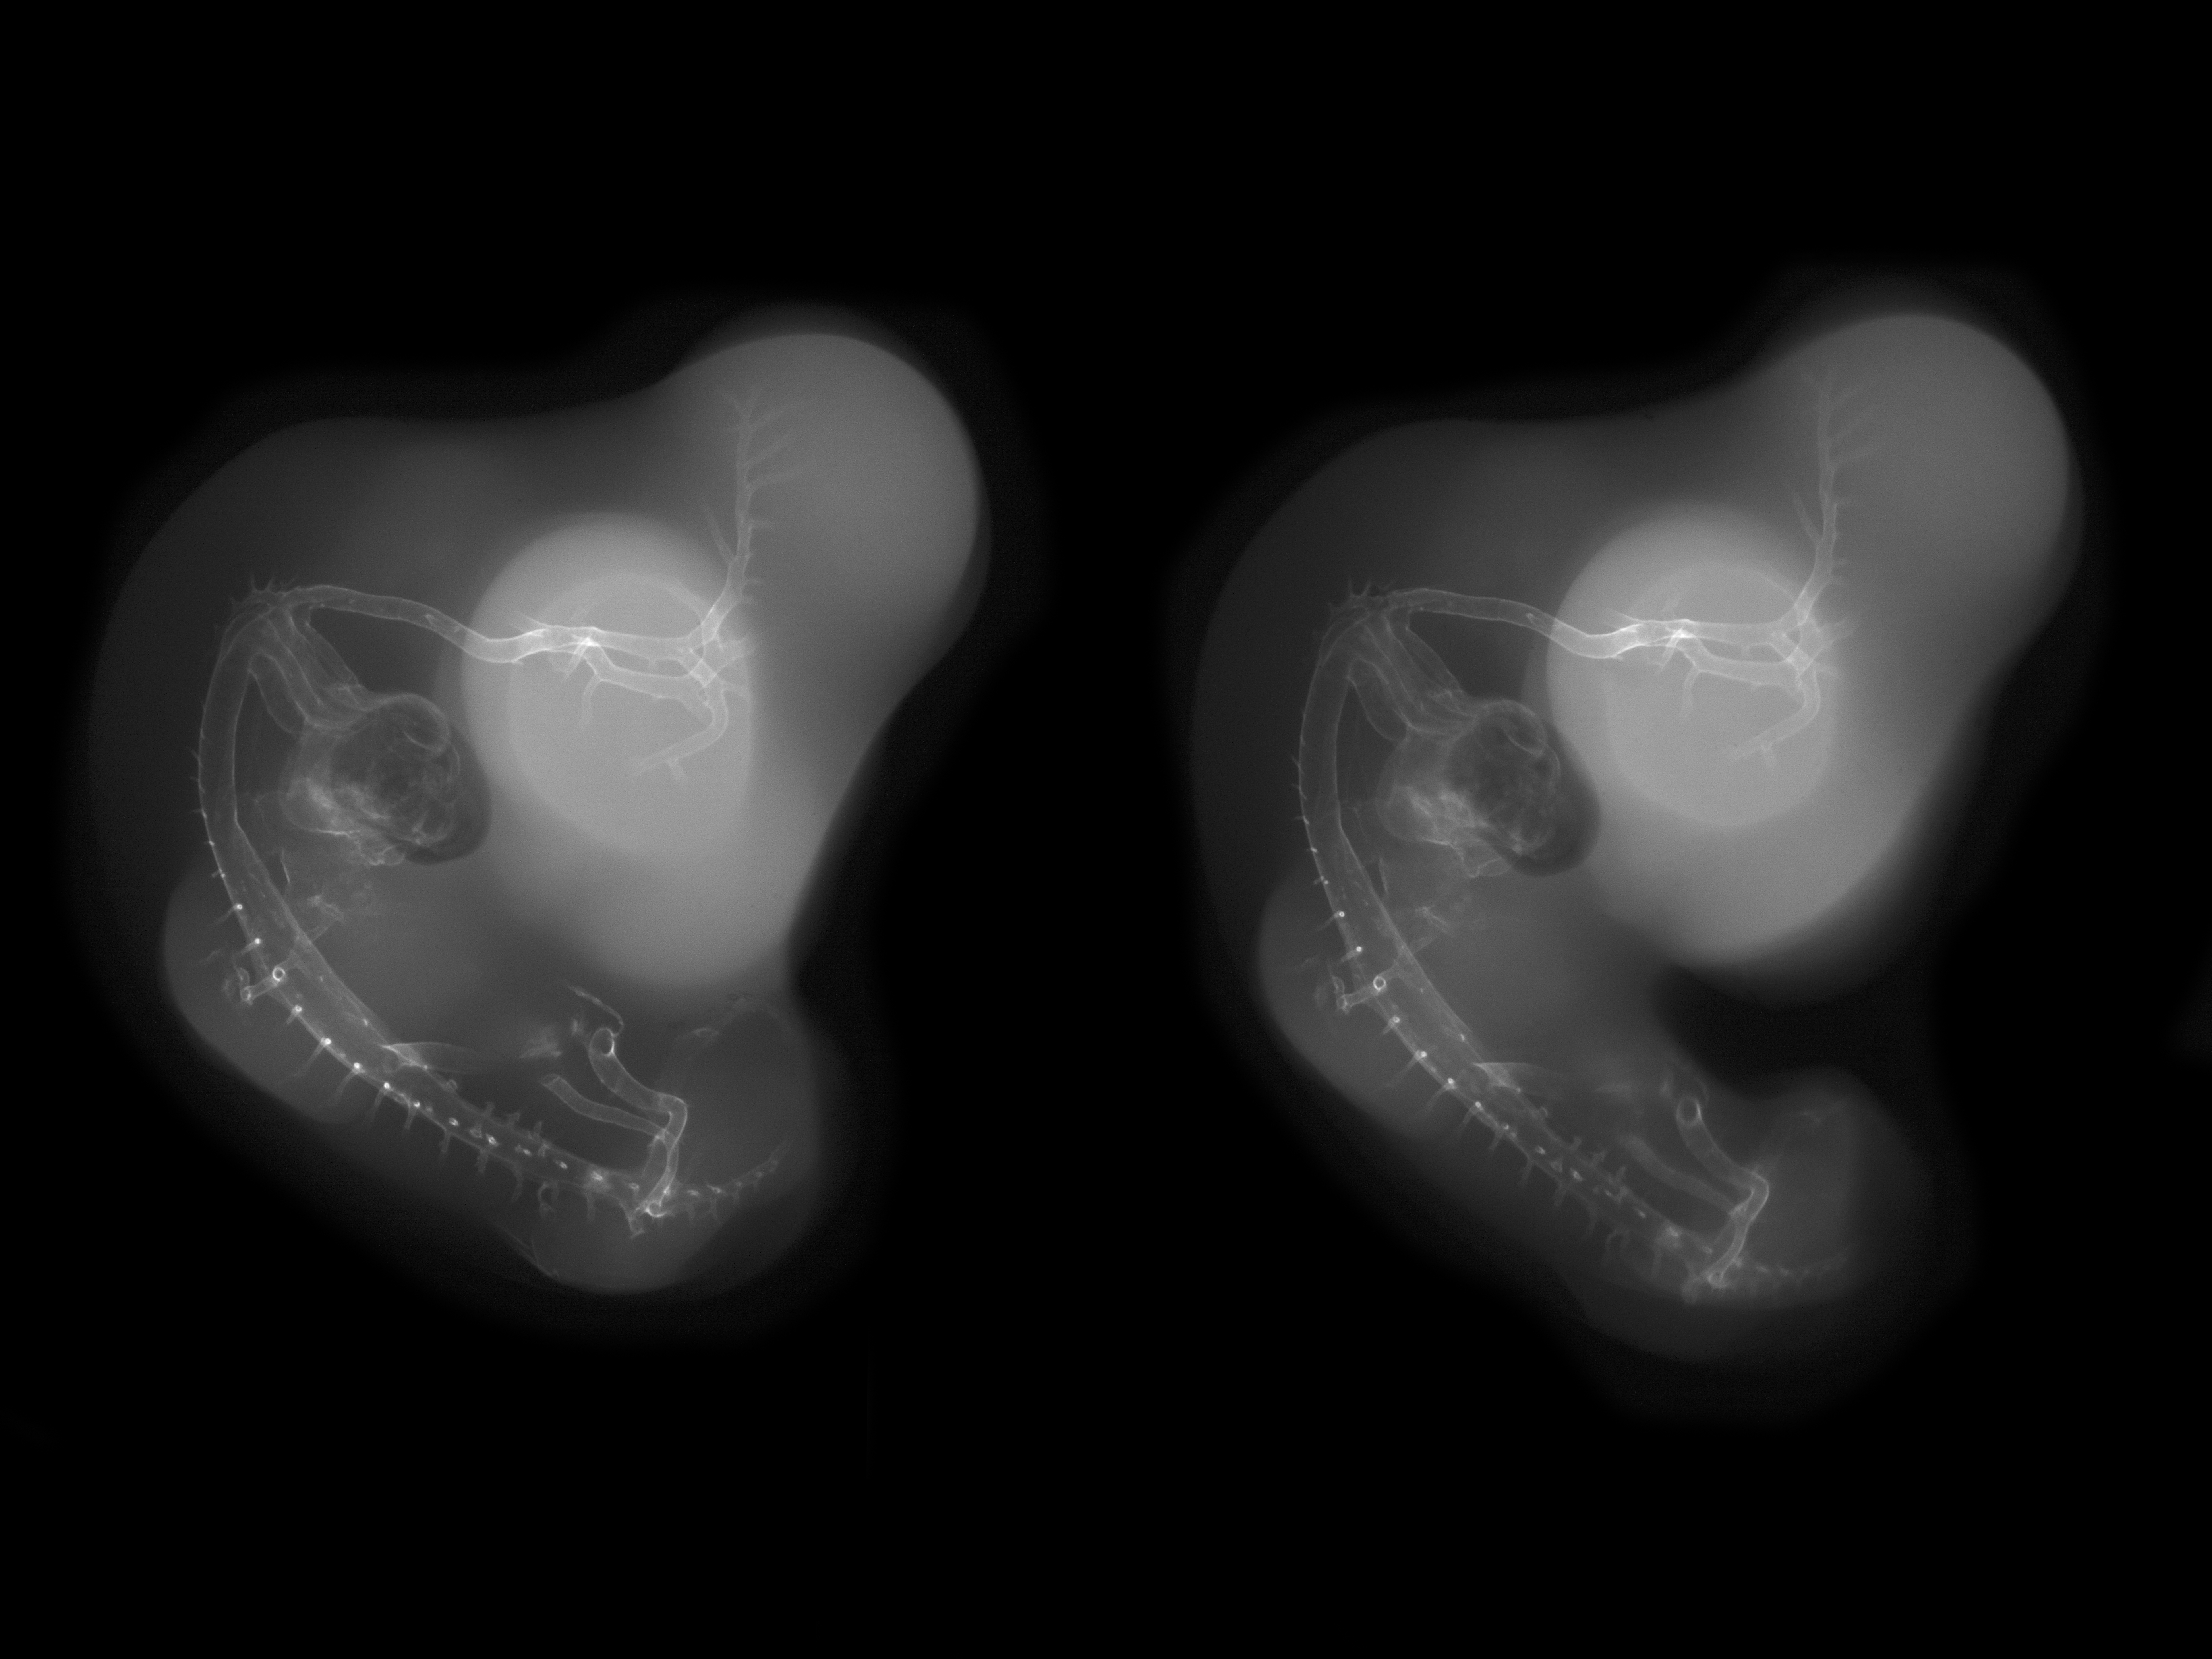

Chick Embryo Microangiography

Hamburger-Hamilton (HH) Stage 27 (approx. 5 - 5.5 days)

Stereo X-Ray Micrographs